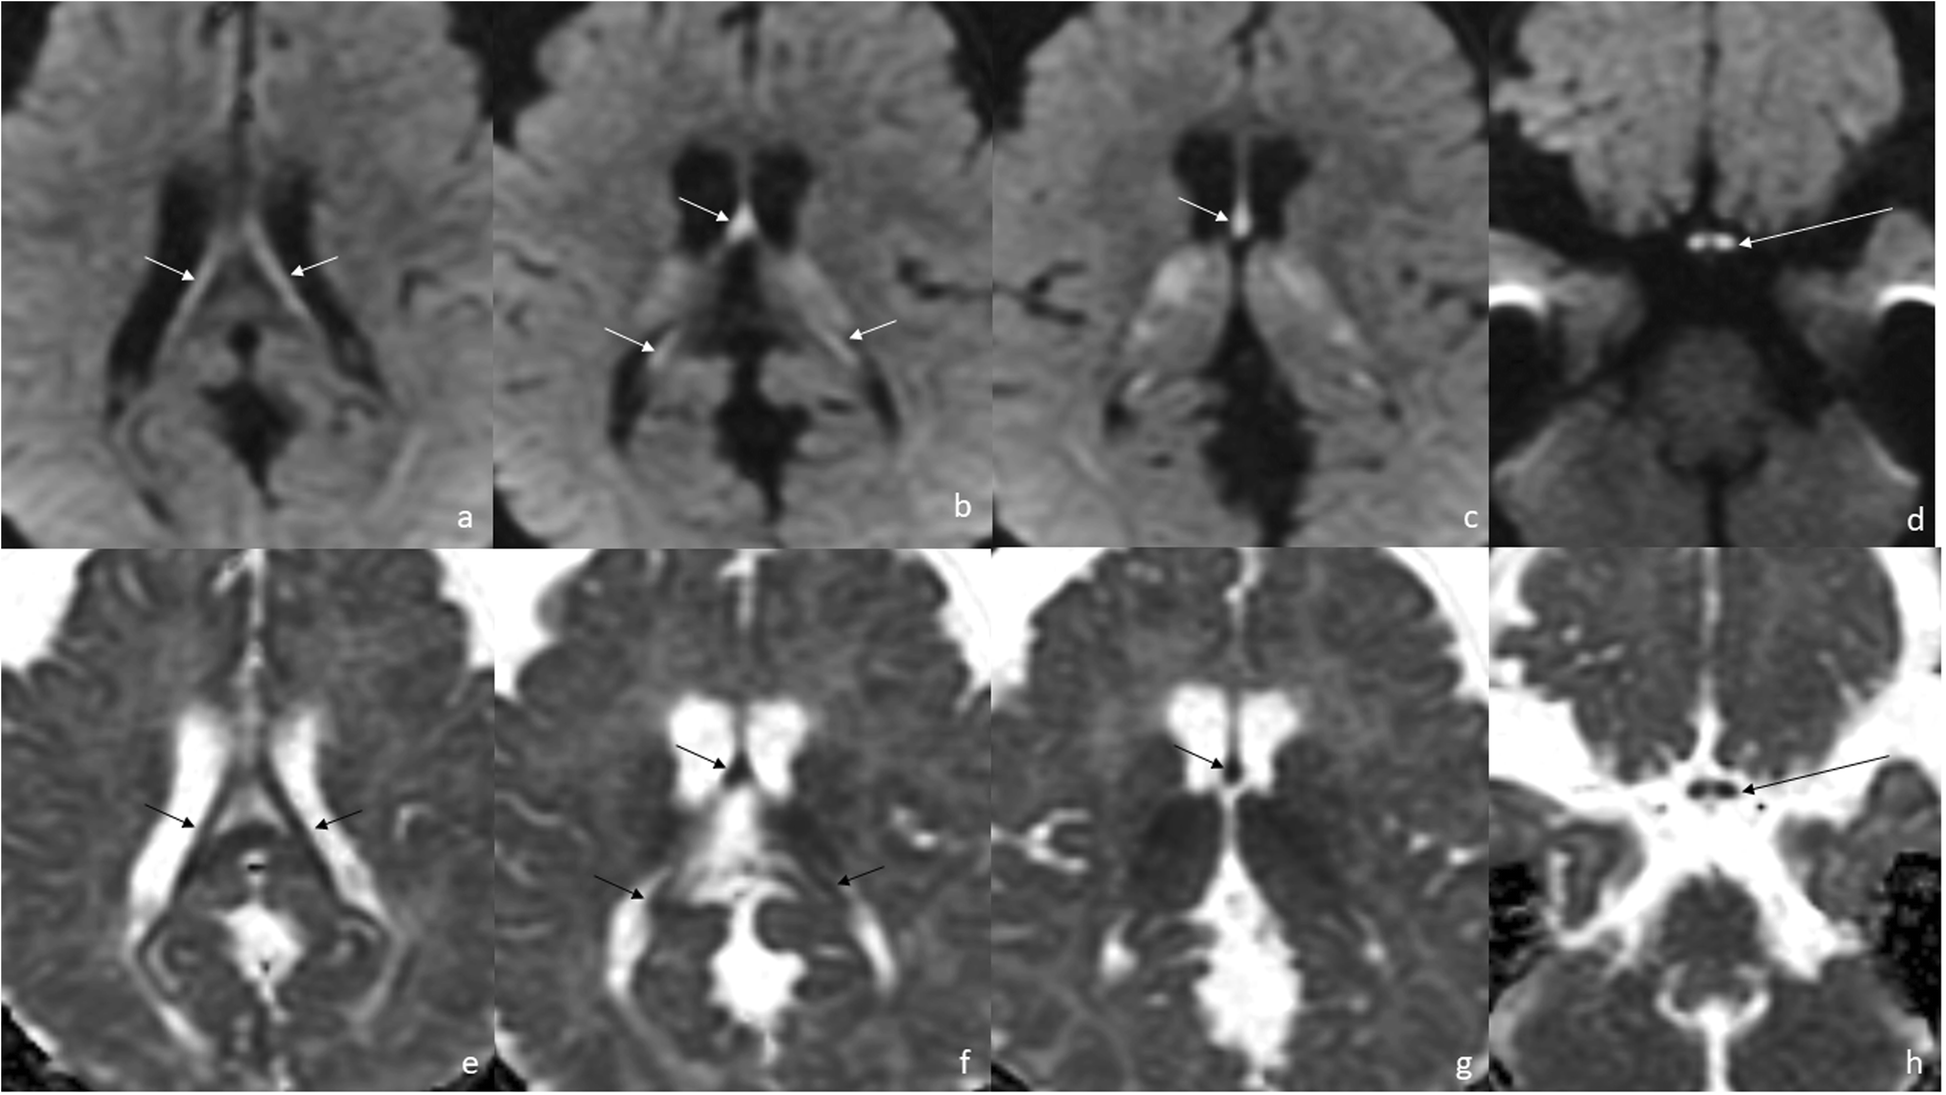

Fig. 2From: Increasing the spectrum of white matter diseases with tigroid pattern on MRI: glutaric aciduria type 1 – case reportScan 1) at the age of 8 months. Diffusion restriction in the fornix (a-c, e-g, short arrows) and in the optic chiasm (d, h) (a-d: DWI, e-h: ADC maps, long arrows). The involvement of the globi pallidi is also seen (c, g)Back to article page